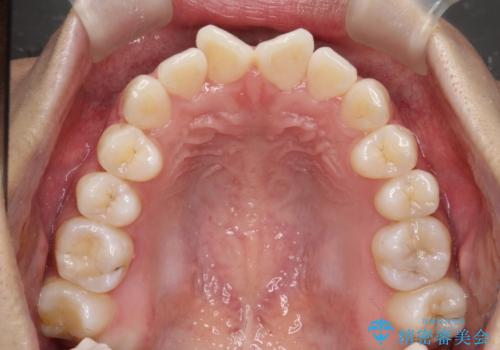

前歯のがたがたを綺麗にしたい

- 前歯がねじれていること、出ていることを主訴に来院されました。

前歯の突出感も改善され、満足していただきました。